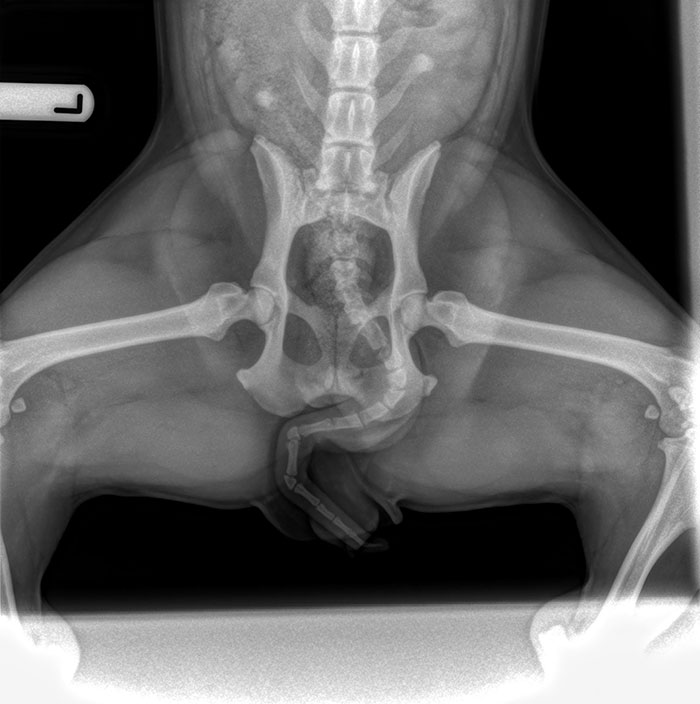

This Xray I Have Of A Pregnant Woman